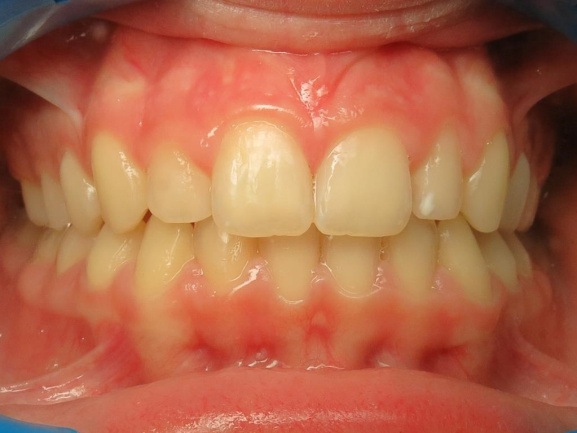

4 - Évolution du visage avant et après traitement.

Le profil est clairement amélioré. Ce traitement est une réussite à la fois fonctionnelle, en rétablissant une occlusion stable, et esthétique, avec un menton bien projeté. L’analyse céphalométrique de Delaire avait anticipé cette croissance favorable, confirmée par le résultat final conforme au diagnostic initial.